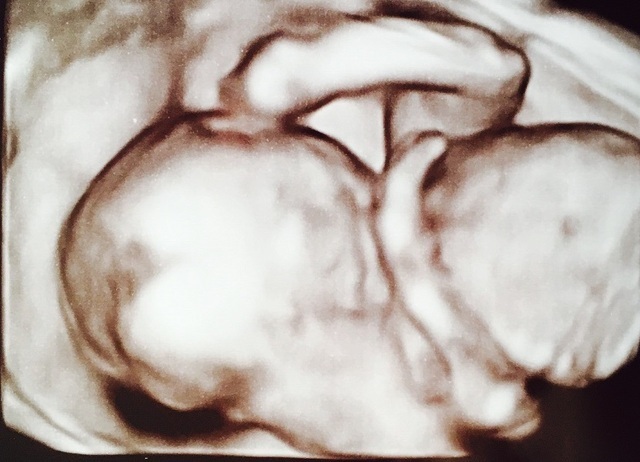

19週1日(19w1d・男の子)|きうらよしこ さん(35歳)

エコー写真撮影時のエピソード:

初めて4Dエコーで我が子を見ることができました。普通のエコーに比べ、鮮明に顔を見ることができ、更に愛しく思えたのを記憶しています。悪阻がきつかったですが、時折写真を眺め、悪阻があるってことは子どもが元気に育っている証拠なんだなぁ等気持ちが前向きになり、どんなお顔なのかな?等話しかけたりしていました。主人も写真を見返しては、どっちに似てるんだろうなぁと嬉しそうに話していました。食事面に関しては、幸い食べ物は何でも食べれたので、あまり神経質にならず好きなものを口にしていました。ですが、出来るだけ自炊をし、赤ちゃんに良いものをと色々ネットで調べて作ったりしました。自分が口にしたものがそのまま我が子へ繋がってるんだなぁ、しっかり栄養とってね等話しかけたりもしてましたね。